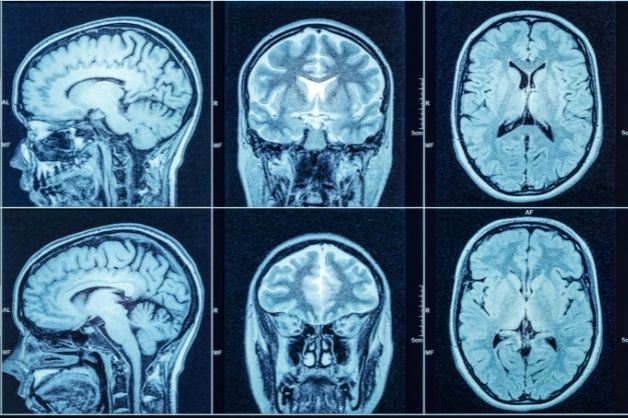

- Sử dụng các phương pháp chẩn đoán hình ảnh như chụp MRI (cộng hưởng từ) hoặc CT não (chụp cắt lớp vi tính sọ não)

Bác sĩ có thể đề nghị người bệnh chụp cộng hưởng từ để chẩn đoán nguyên nhân gây ra tình trạng co giật